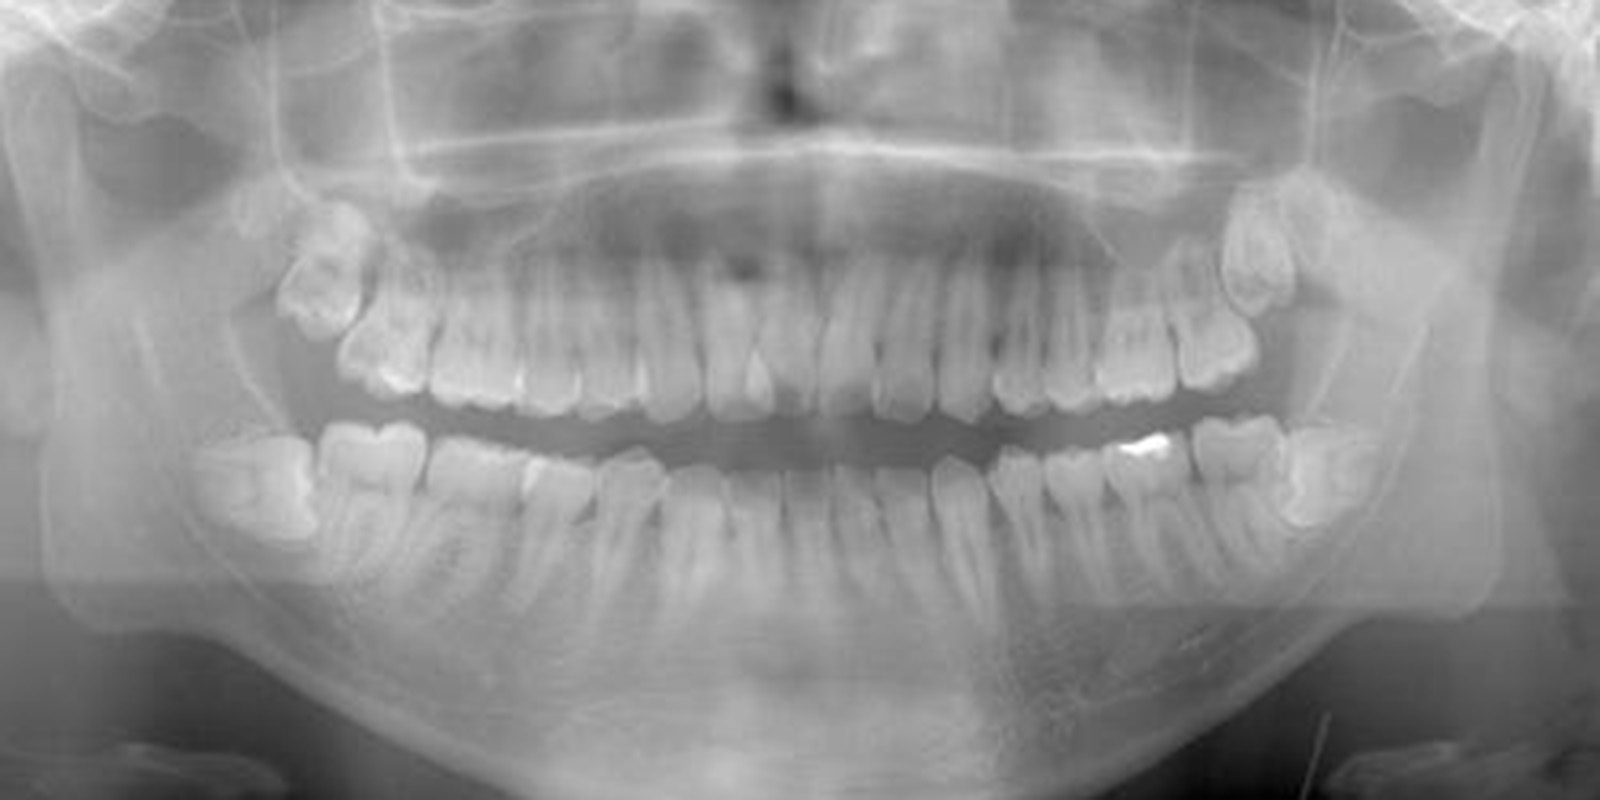

レントゲン画像の親知らず

親知らずがあるレントゲン画像

ただ根の先に下顎管が触れているようなケースであれば2回で対応したりしますが歯の頭の部分が下顎管と触れているような稀なケース、親知らず周りが嚢胞になってしまっているケース、全身疾患がある方、外科処置が困難な方に関しては大学病院を紹介させていただくこともあります。